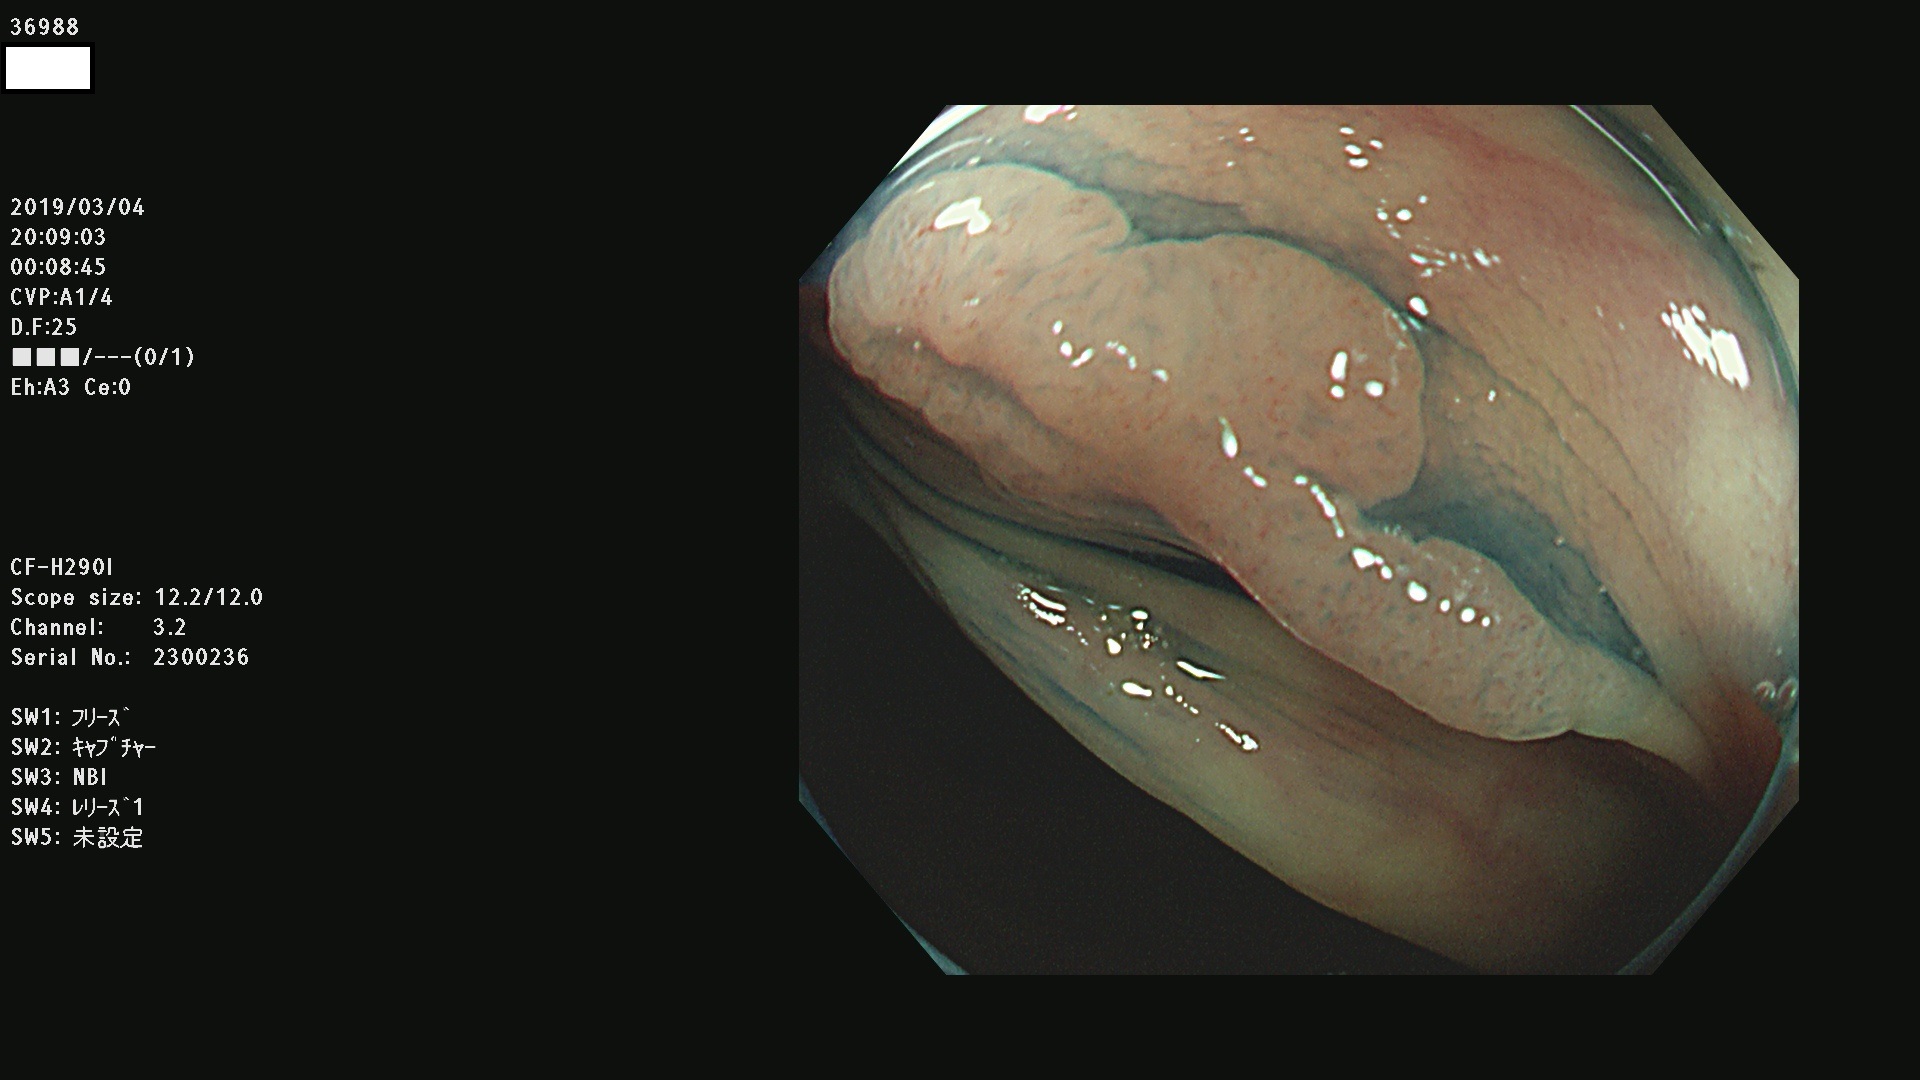

腺腫発見率 67 % (カルテ番号 36900〜36999の100名の方の検査結果で集計)大腸癌検診最新情報

以下のカルテ番号の方に腺腫(Adenoma,Group3〜5)が見つかりました(集計法)

36900 36901 36903 36904 36905 36908 36909 36910 36911 36913 36914 36915 36916 36917 36918 36919 36920 36923 36924 36925 36927 36928 36930 36931(SSAPのみ) 36933 36935 36936 36937 36941 36943 36944 36945 36946 36949 36951 36953 36954 36955 36957 36963 36965 36966 36967 36968 36969 36970 36974 36975 36976 36977 36978 36979 36980 36981 36983 36984 36986 36987 36988 36989 36990 36991 36993 36994 36996 36998 36999

発見困難で危険性の高い平坦型病変(上記100名より抽出) ![]()